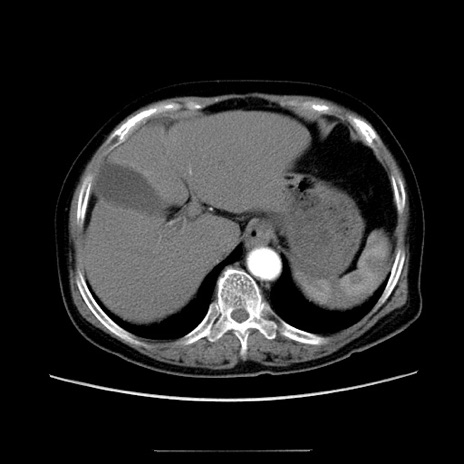

症例5(横断像)

【症例】70歳代女性

【主訴】お腹が張る

【現病歴】1週間くらい前から腹部膨満の自覚あり。昨日夜から増悪したため、本日救急外来受診。

【身体所見】意識清明、BT 36.5℃、BP 165/106mmHg、HR 80bpm、SpO2 98%、腹部:膨満、軟、自発痛・圧痛なし、触診にて不快感あり、腸蠕動音:減弱

【データ】WBC 12600、CRP 1.04